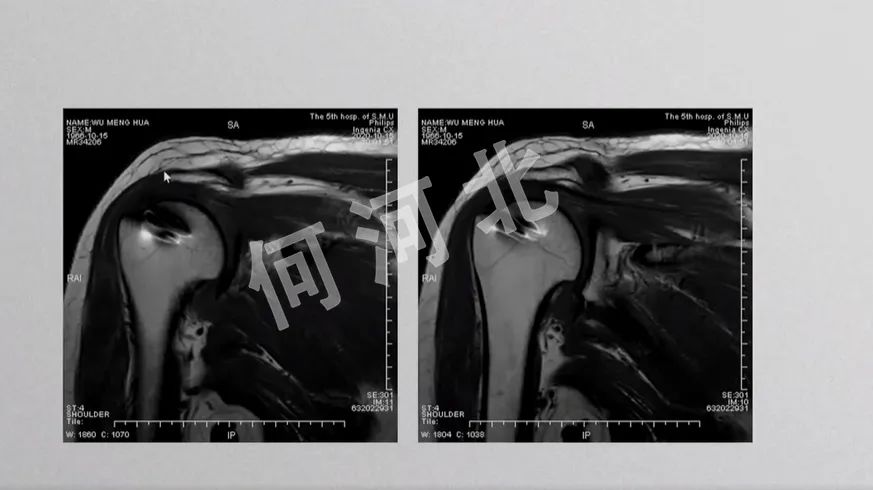

术前影像

MRI